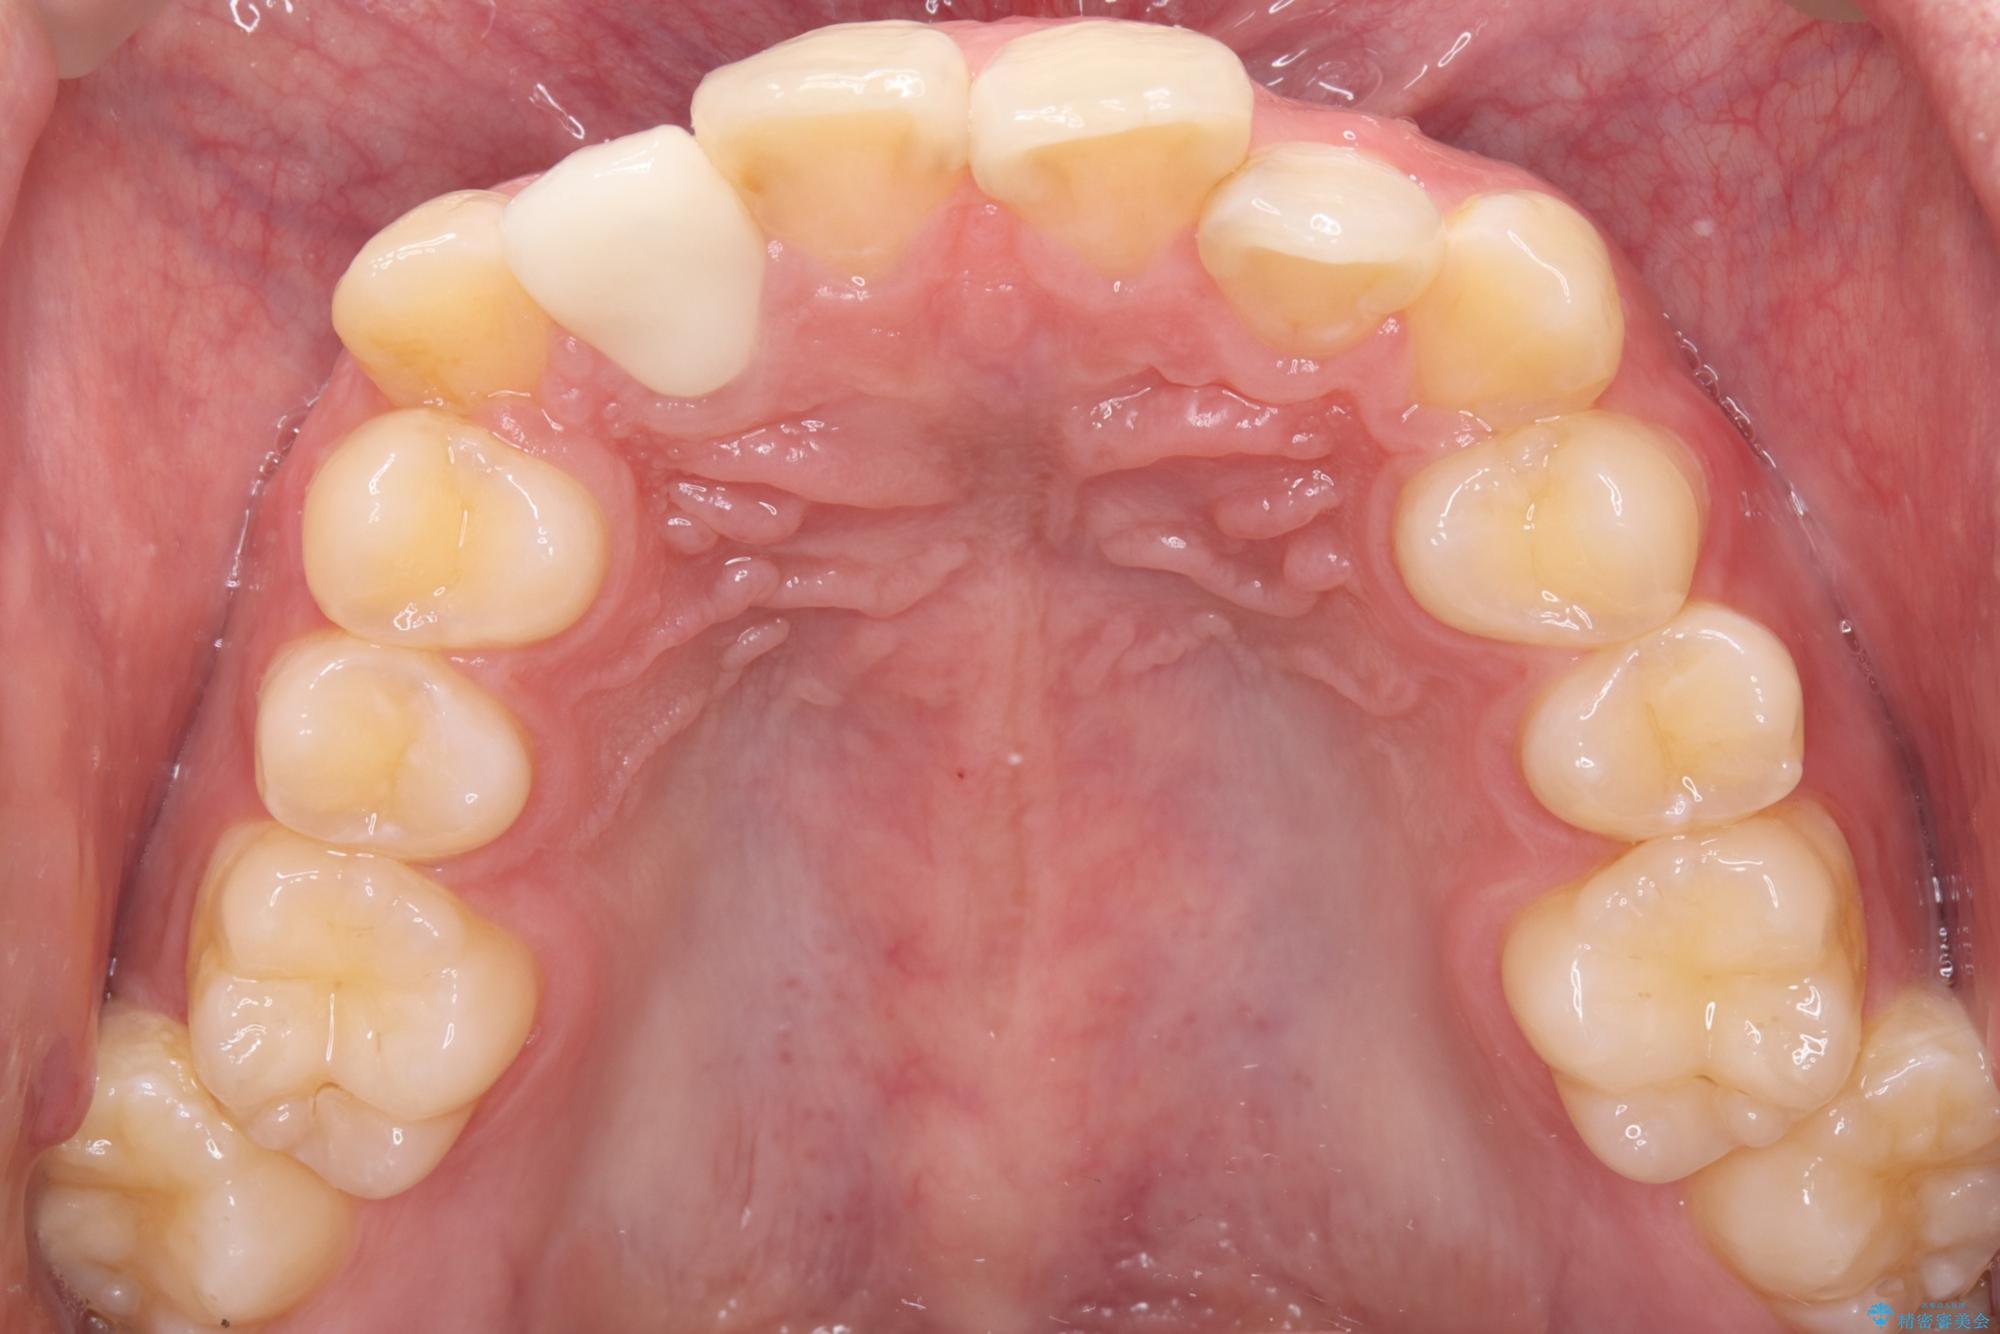

右上2番の歯に自発痛を認め、症状や歯髄診・レントゲン像から不可逆性歯髄炎と診断し、精密根管治療から歯冠補綴まで行うこととなりました。

初診時に歯髄診断を行い、不可逆性歯髄炎と診断し抜髄から補綴修復までの流れを説明し、精密根管治療、ファイバ-コア築造、オールセラミッククラウン(St)修復を行うこととしました。